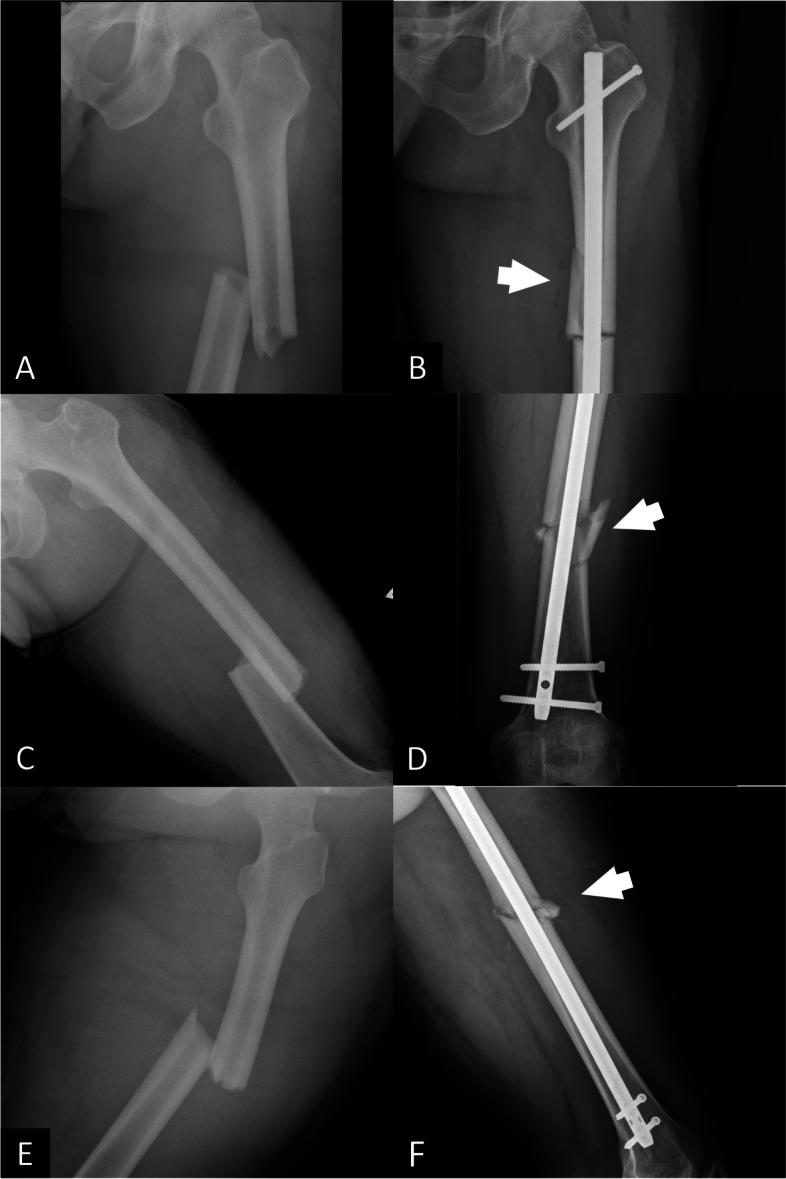

顺行交锁髓内钉治疗单纯股骨干骨折所致医源性骨折粉碎的特点及影响:一项回顾性队列研究。

The characteristics and influence of iatrogenic fracture comminution following antegrade interlocking nailing for simple femoral shaft fractures, a retrospective cohort study.

The incidence and characteristics of iatrogenic comminution (IC) are unknown, and the influence of IC on fracture union is unclear. This study was aimed to investigate the (1) incidence and characteristics of IC and (2) the outcomes of IC following antegrade interlocking nailing of simple femoral shaft fractures.

RESULTS

Of the 211 total patients, IC occurred in 20.9% (n = 44) of patients. Most ICs were found at the level of the isthmus, and involved the medial cortex. Compared with the NIC group, higher nonunion rates were observed in the IC group at 12 months (31.8% vs. 12.5%, p = 0.002) and 24 months (18% vs. 6.5%, p = 0.017) after surgery. Age older than 35 years old was related with the occurrence of IC in univariate analysis. Multivariate analysis found no risk factor associated with IC. Open reduction technique, IC occurrence and higher BMI were identified as the risk factors of nonunion at 12 months and 24 months after surgery in multivariate analysis.

医源性粉碎性骨折(IC)的发生率和特征尚不清楚,其对骨折愈合的影响也不明确。本研究旨在探讨(1)IC 的发生率和特征,以及(2)顺行交锁髓内钉治疗单纯股骨干骨折后 IC 的结果。

结果

在 211 例患者中,IC 的发生率为 20.9%(n=44)。大多数 IC 发生在峡部水平,累及内侧皮质。与 NIC 组相比,IC 组在术后 12 个月(31.8%比 12.5%,p=0.002)和 24 个月(18%比 6.5%,p=0.017)的不愈合率更高。年龄大于 35 岁与单变量分析中的 IC 发生有关。多变量分析发现,IC 无相关危险因素。多变量分析发现,切开复位技术、IC 发生和较高 BMI 是术后 12 个月和 24 个月发生骨折不愈合的危险因素。